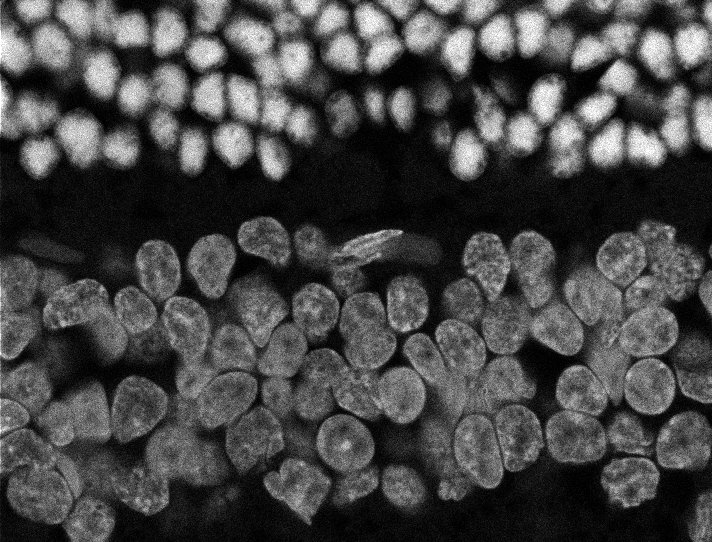

Nuclei

Nuclei - Bip